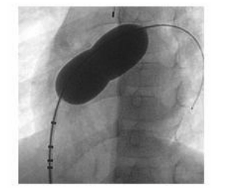

- Sử dụng bóng đo kích thước TLN.

+ Đẩy bóng trên guidewire cứng lên lỗ thông liên nhĩ. Bơm bóng bằng thuốc cản quang tại vị trí lỗ TLN. Ngừng bơm khi xuất hiện rõ eo bóng.

+ Sử dụng siêu âm qua thực quản để quan sát xem bóng đã bít hoàn toàn lỗ thông chưa.

+ Đo kích thước eo bóng trên phim chụp mạch dựa vào các điểm mốc trên bóng.

+ Làm xẹp bóng, rút bóng ra khỏi cơ thể. Đo lại kích thước bóng bằng cách bơm một lượng thuốc cản quang tương tự.

+ Xác định kích thước lỗ TLN theo ba phương pháp: trên phim chụp mạch, trên siêu âm qua thực quản, và phương pháp đo trực tiếp ở ngoài.

Hình 17.1: Đo kích thước lỗ thông bằng bóng